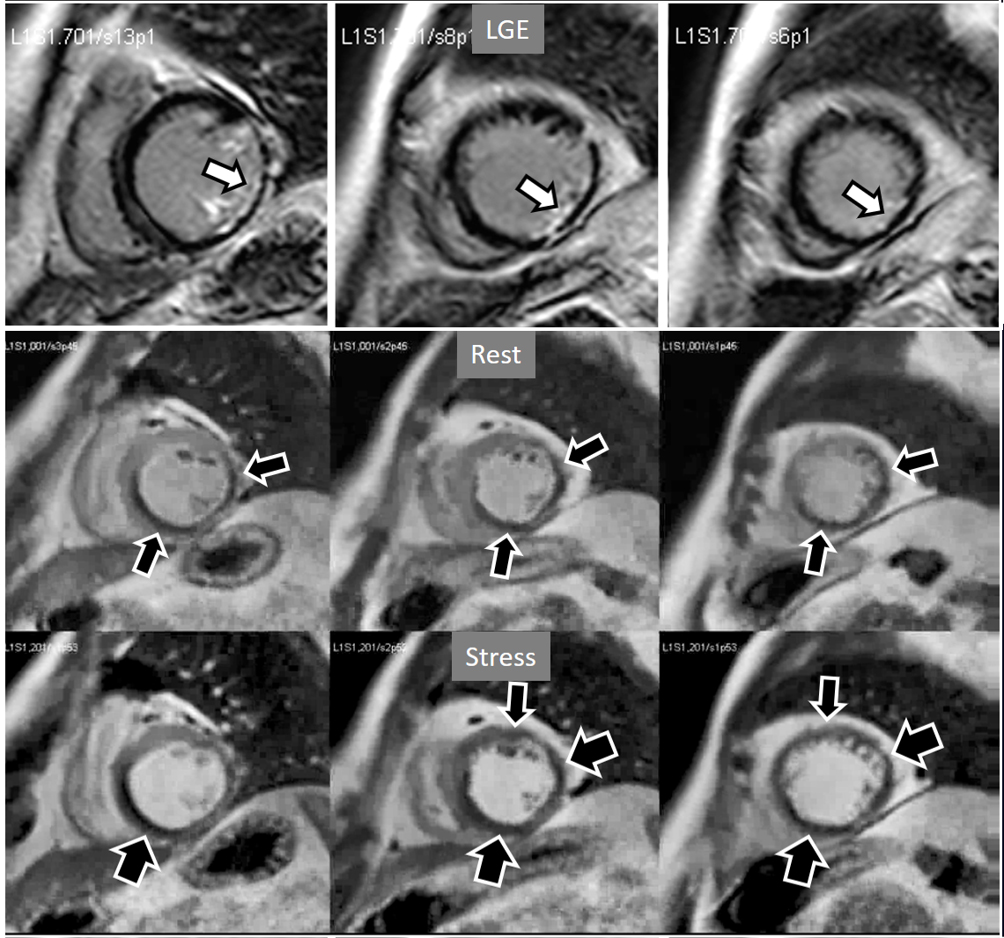

Perfusion defects in different territories can be detected in case of multivessel disease (Fig. 7) and, in patients with severe 3-vessel CAD, the perfusion study may show a global, intense, persistent defect which is readily recognizable (Fig. 8).

Fig. 7.Two-vessel perfusion defect. Stress perfusion defects at the anterior (white arrows) and inferior (black arrows) walls, not present at rest. Angiography (right panels) shows significant stenoses (white arrows) of the LAD (upper panel) and the right coronary artery (RCA) (lower panel).